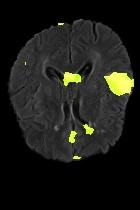

Current unsupervised anomaly localization approaches rely on generative models to learn the distribution of normal images, which is later used to identify potential anomalous regions derived from errors on the reconstructed images. However, a main limitation of nearly all prior literature is the need of employing anomalous images to set a class-specific threshold to locate the anomalies. This limits their usability in realistic scenarios, where only normal data is typically accessible. Despite this major drawback, only a handful of works have addressed this limitation, by integrating supervision on attention maps during training. In this work, we propose a novel formulation that does not require accessing images with abnormalities to define the threshold. Furthermore, and in contrast to very recent work, the proposed constraint is formulated in a more principled manner, leveraging well-known knowledge in constrained optimization. In particular, the equality constraint on the attention maps in prior work is replaced by an inequality constraint, which allows more flexibility. In addition, to address the limitations of penalty-based functions we employ an extension of the popular log-barrier methods to handle the constraint. Comprehensive experiments on the popular BRATS'19 dataset demonstrate that the proposed approach substantially outperforms relevant literature, establishing new state-of-the-art results for unsupervised lesion segmentation.